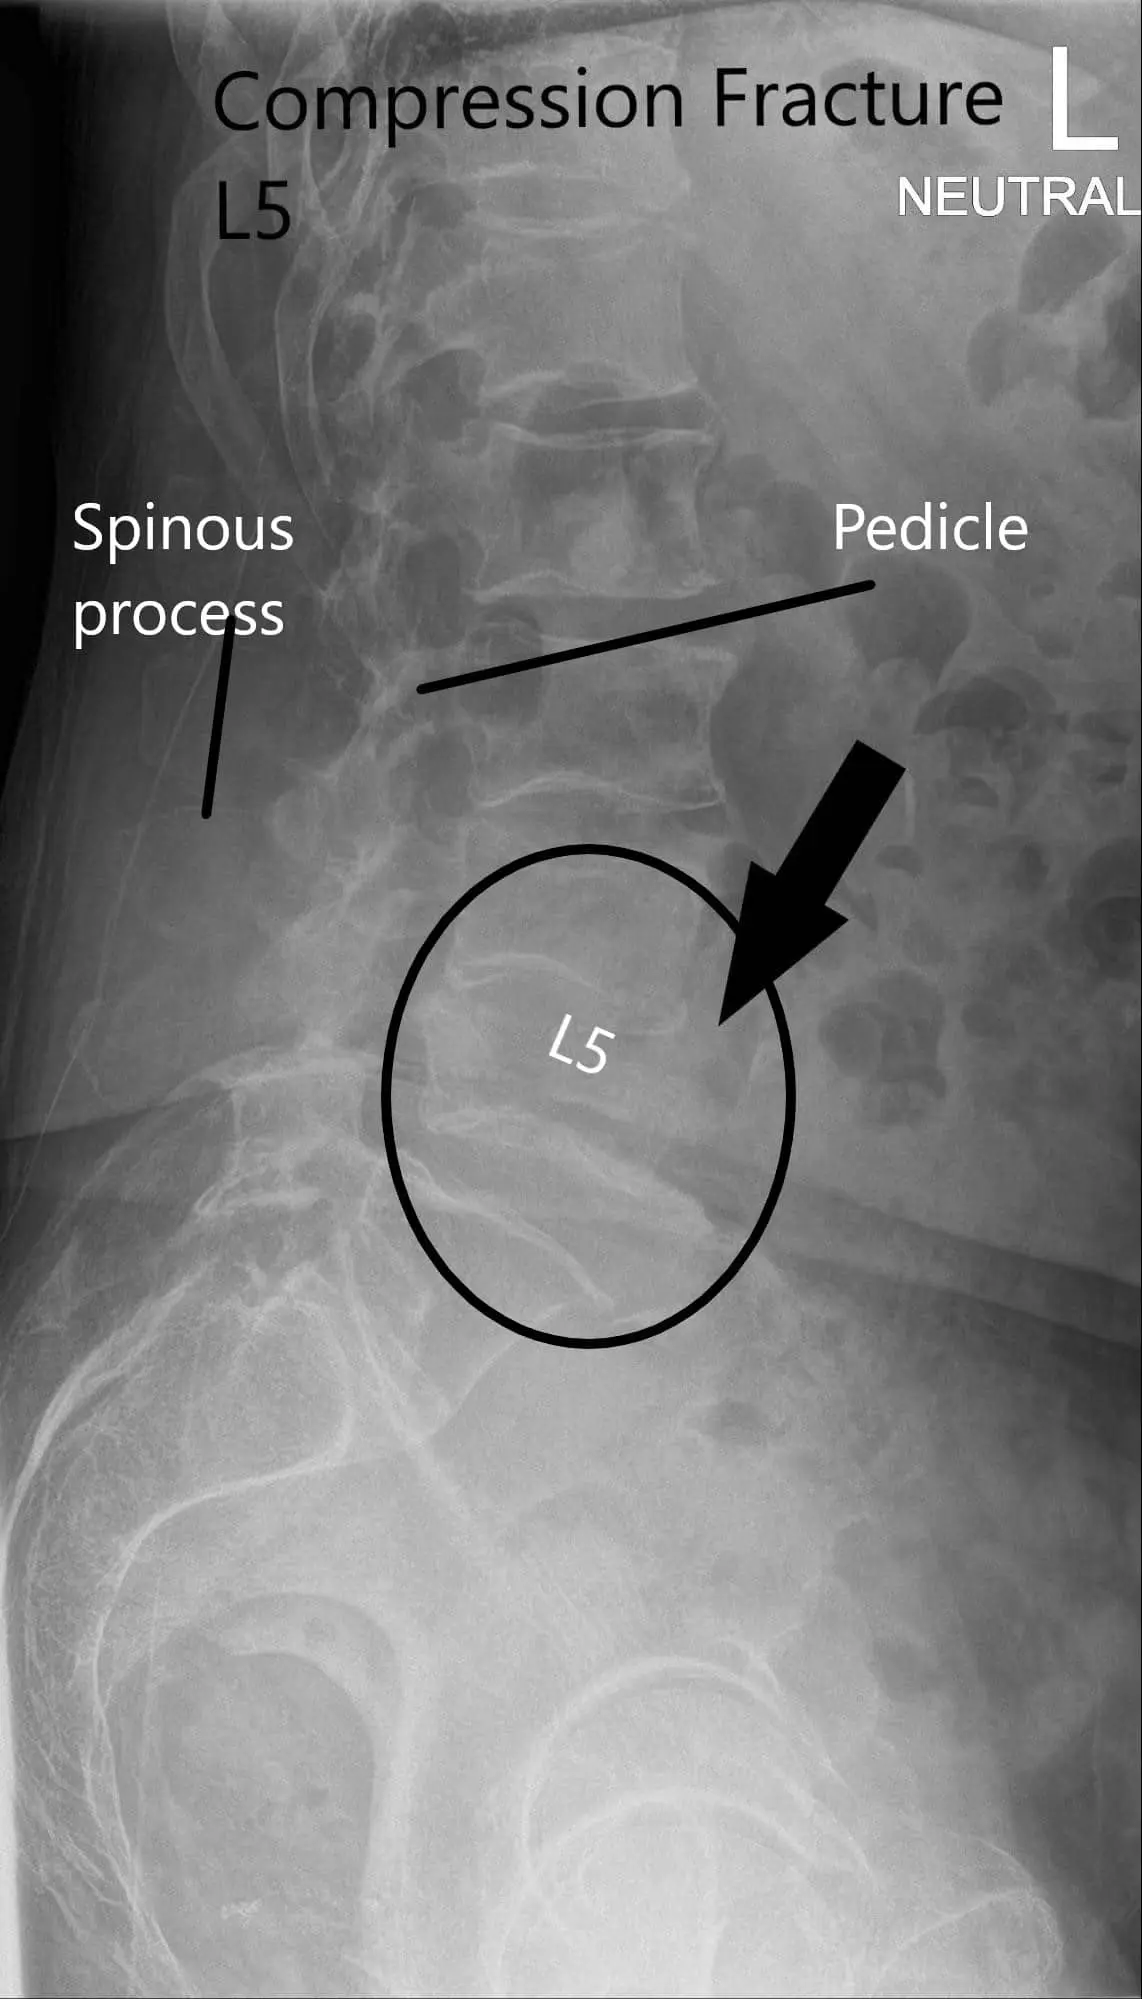

X-ray of LS spine in AP and Lateral views showing significant compression fracture L5.

CT suggested a severe compression fracture of L5 with mild retropulsion of superior endplate. Multilevel degenerative spondylosis of the lumbar spine. Moderate to severe spinal canal stenosis at L3-L4 and L4-L5 levels.

MRI lumbar spine suggested acute or subacute compression fracture at L5. Degenerative changes with multilevel spinal canal or neural foraminal, subarticular recess stenosis were also present at L4-5 and L5-S1.